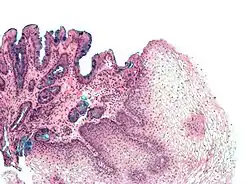

Both macroscopic (from endoscopy) and microscopic positive findings are required to make a diagnosis. Barrett's esophagus is marked by the presence of columnar epithelia in the lower esophagus, replacing the normal squamous cell epithelium—an example of metaplasia. The secretory columnar epithelium may be more able to withstand the erosive action of the gastric secretions; however, this metaplasia confers an increased risk of adenocarcinoma.[14]

Intestinal metaplasia

The presence of goblet cells, called intestinal metaplasia, is necessary to make a diagnosis of Barrett's esophagus. This frequently occurs in the presence of other metaplastic columnar cells, but only the presence of goblet cells is diagnostic. The metaplasia is grossly visible through a gastroscope, but biopsy specimens must be examined under a microscope to determine whether cells are gastric or colonic in nature. Colonic metaplasia is usually identified by finding goblet cells in the epithelium and is necessary for the true diagnosis.

Many histologic mimics of Barrett's esophagus are known (i.e. goblet cells occurring in the transitional epithelium of normal esophageal submucosal gland ducts, "pseudogoblet cells" in which abundant foveolar [gastric] type mucin simulates the acid mucin true goblet cells). Assessment of relationship to submucosal glands and transitional-type epithelium with examination of multiple levels through the tissue may allow the pathologist to reliably distinguish between goblet cells of submucosal gland ducts and true Barrett's esophagus (specialized columnar metaplasia). The histochemical stain Alcian blue pH 2.5 is also frequently used to distinguish true intestinal-type mucins from their histologic mimics. Recently, immunohistochemical analysis with antibodies to CDX-2 (specific for mid and hindgut intestinal derivation) has also been used to identify true intestinal-type metaplastic cells. The protein AGR2 is elevated in Barrett's esophagus[16] and can be used as a biomarker for distinguishing Barrett epithelium from normal esophageal epithelium.[17]